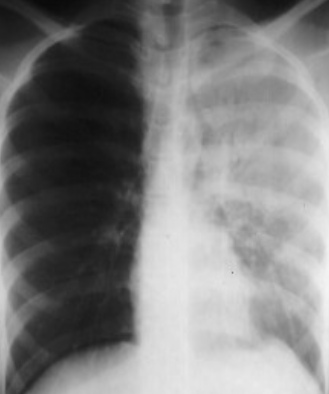

Consolidation of RT. middle lobe in PA and LA view

The left hemithorax is opaque

- There is no shift of the heart or trachea

- The opacified hemithorax contains air bronchogram

- No loss of lung volume